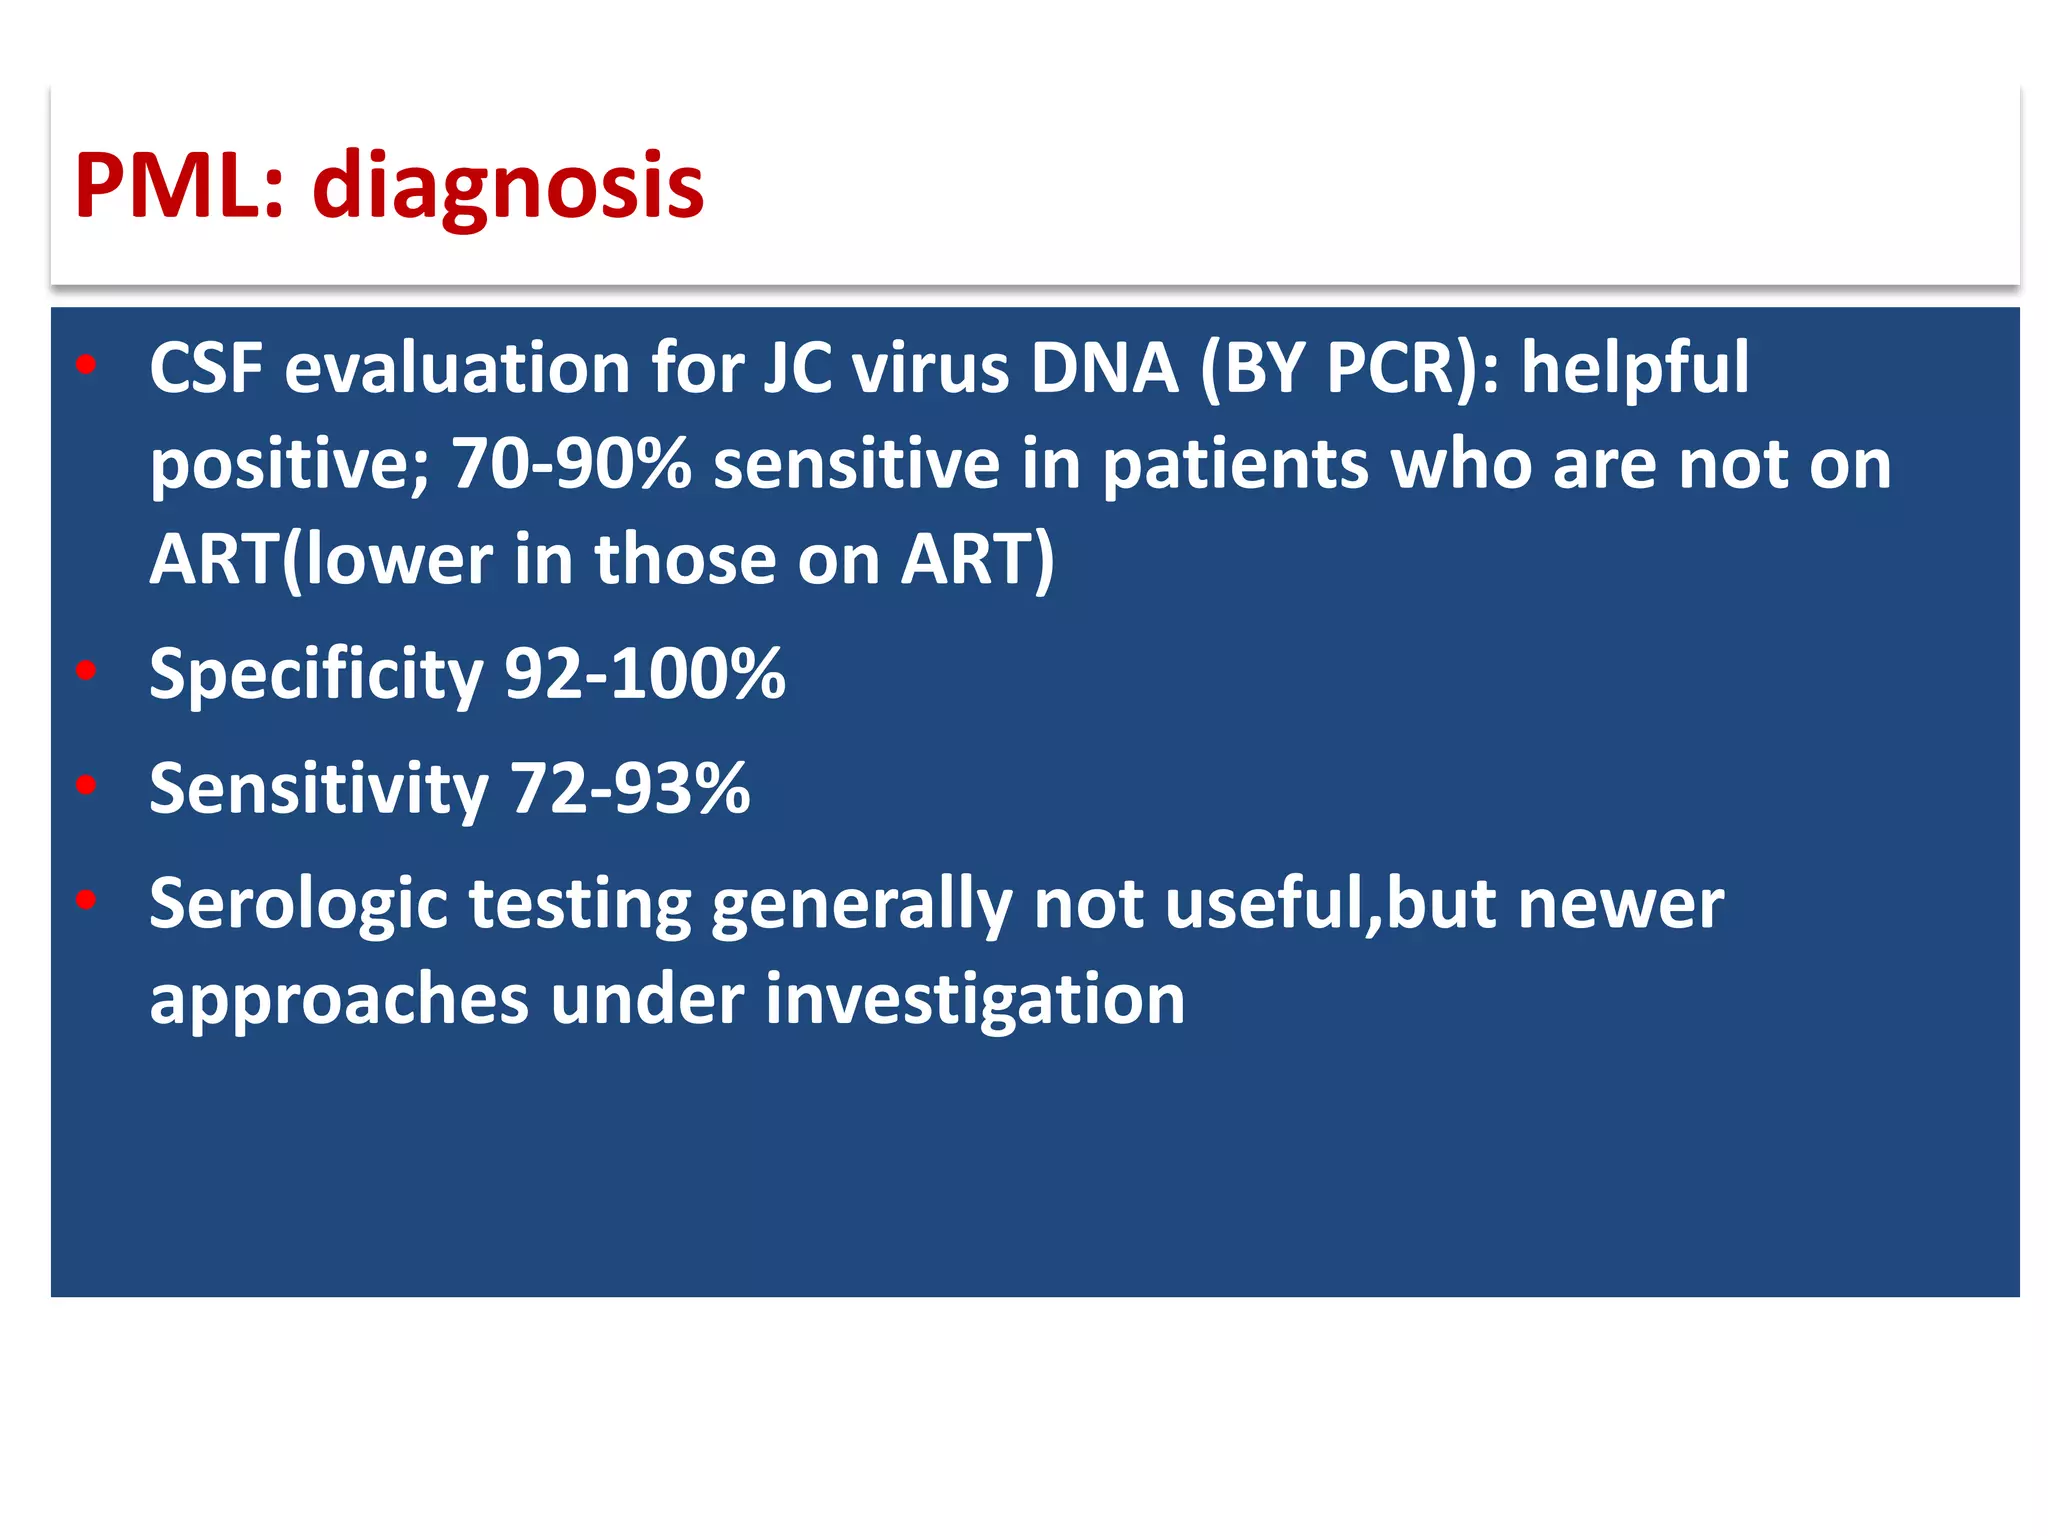

This document discusses progressive multifocal leukoencephalopathy (PML), an opportunistic infection caused by the John Cunningham virus (JCV) that leads to demyelination in the central nervous system. It highlights the epidemiology, clinical manifestations, diagnostic methods, and risk factors associated with PML, particularly in immunocompromised patients and those undergoing immunomodulatory therapies. It also presents data on the incidence of PML in patients treated with natalizumab and other therapies, addressing the relationships between these treatments and the development of PML.